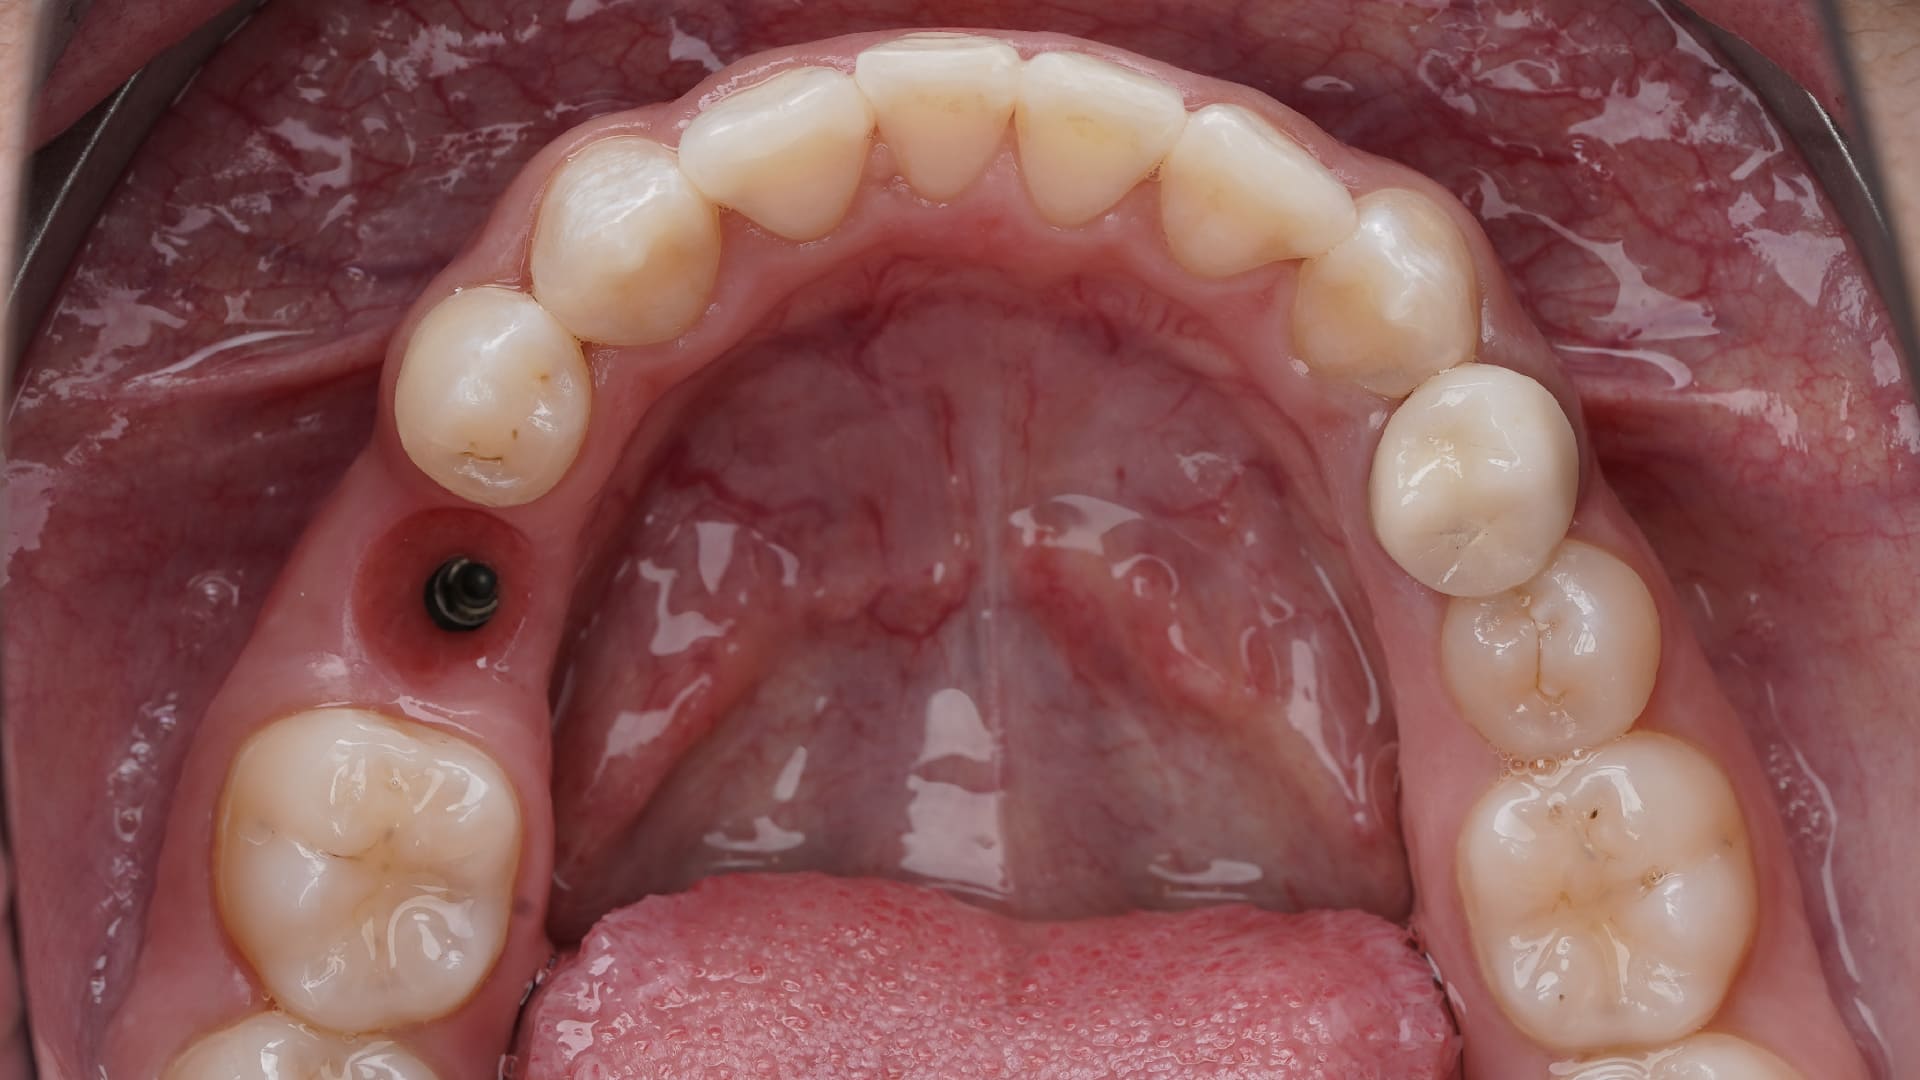

Customized healing in the posterior sites

CLINICAL CASES